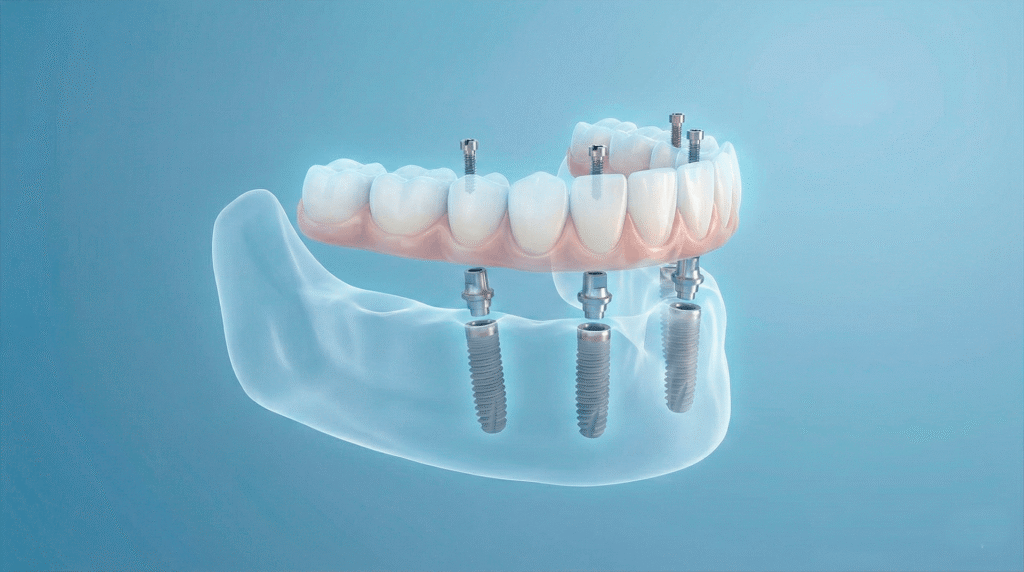

Metoda All-on-4 to zaawansowane rozwiązanie protetyczne, które pozwala na pełną rekonstrukcję łuku zębowego przy użyciu zaledwie czterech implantów. Jest to sprawdzona droga do odzyskania stałego uzębienia, szczególnie polecana pacjentom zmagającym się z zanikiem kości w żuchwie.

System ten opiera się na precyzyjnym rozmieszczeniu czterech punktów podparcia, które utrzymują cały most protetyczny:

Dwa implanty centralne

Wprowadzane równolegle do siebie (zazwyczaj w miejscach „dwójek”).

Dwa implanty boczne

Wprowadzane pod kątem około 20 stopni (w miejscach „czwórek” lub „piątek”).

Zastosowanie kąta nachylenia pozwala na optymalne wykorzystanie dostępnej tkanki kostnej, co często eliminuje konieczność przeprowadzania skomplikowanych zabiegów jej odbudowy.

Chcą Panstwo dowiedzieć się, czy warunki anatomiczne pozwalają na zastosowanie metody All-on-4? Zapraszamy na konsultację, podczas której wykonamy niezbędną diagnostykę.